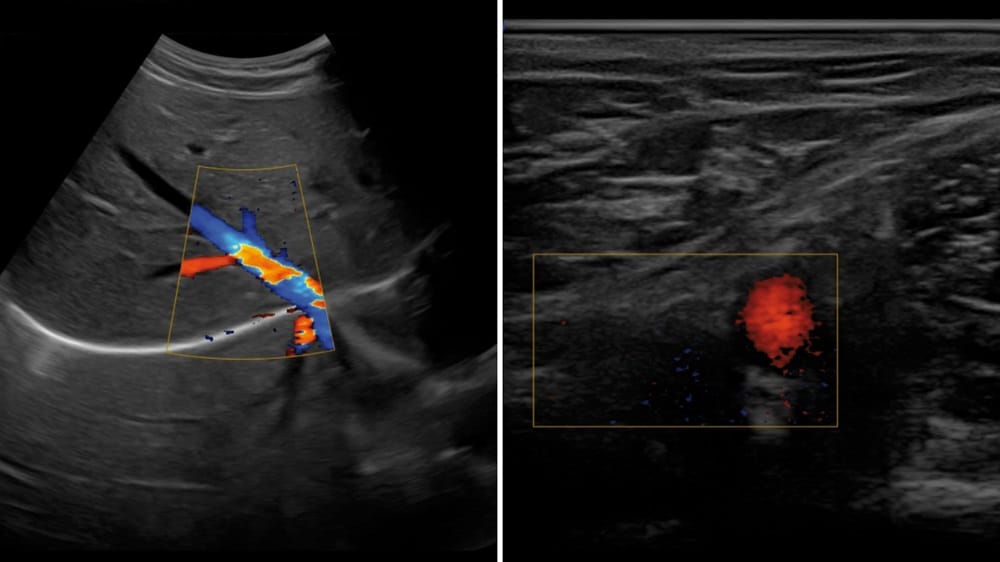

With ultrasound scanners, an electronic probe is placed on the part of the body being operated on—for example, the fingers, shoulders, or feet, where the nerves are—and a gel is rubbed over the skin to get the scanner to produce images. The physician injects the liquid anesthetic into the patient to prevent them feeling pain during surgery. The images allow the anesthesiologist to see and follow where the needle enters the body—and where the injected solution goes.